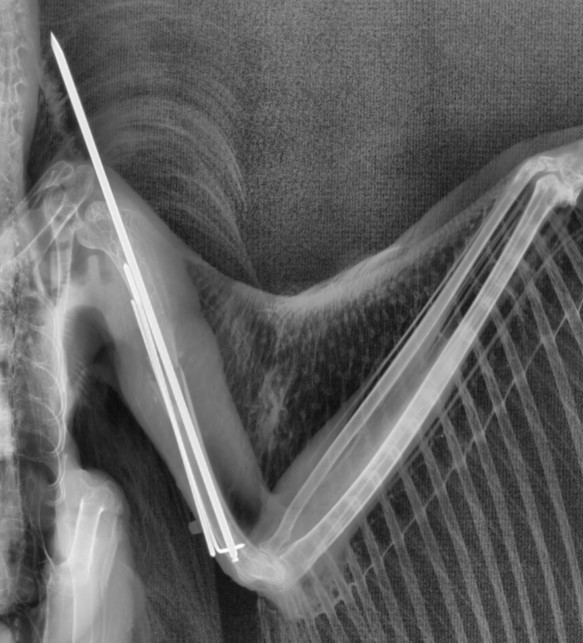

Un ejemplo destacado es el caso de un búho real que ingresó en nuestro hospital de fauna con una fractura del húmero que nuestro personal veterinario estabilizó mediante cirugía con una combinación de fijador externo y aguja intramedular. Una complicación posible en estos procedimientos es la infección en la zona de entrada de la aguja. En este escenario, el VITEK®2 permitió al equipo de GREFA identificar rápidamente el patógeno responsable y administrar un tratamiento preciso basado en los resultados del antibiograma, mejorando significativamente el pronóstico de esta ave rapaz.

Radiografía en la que se aprecia el fijador externo y la aguja intramedular.